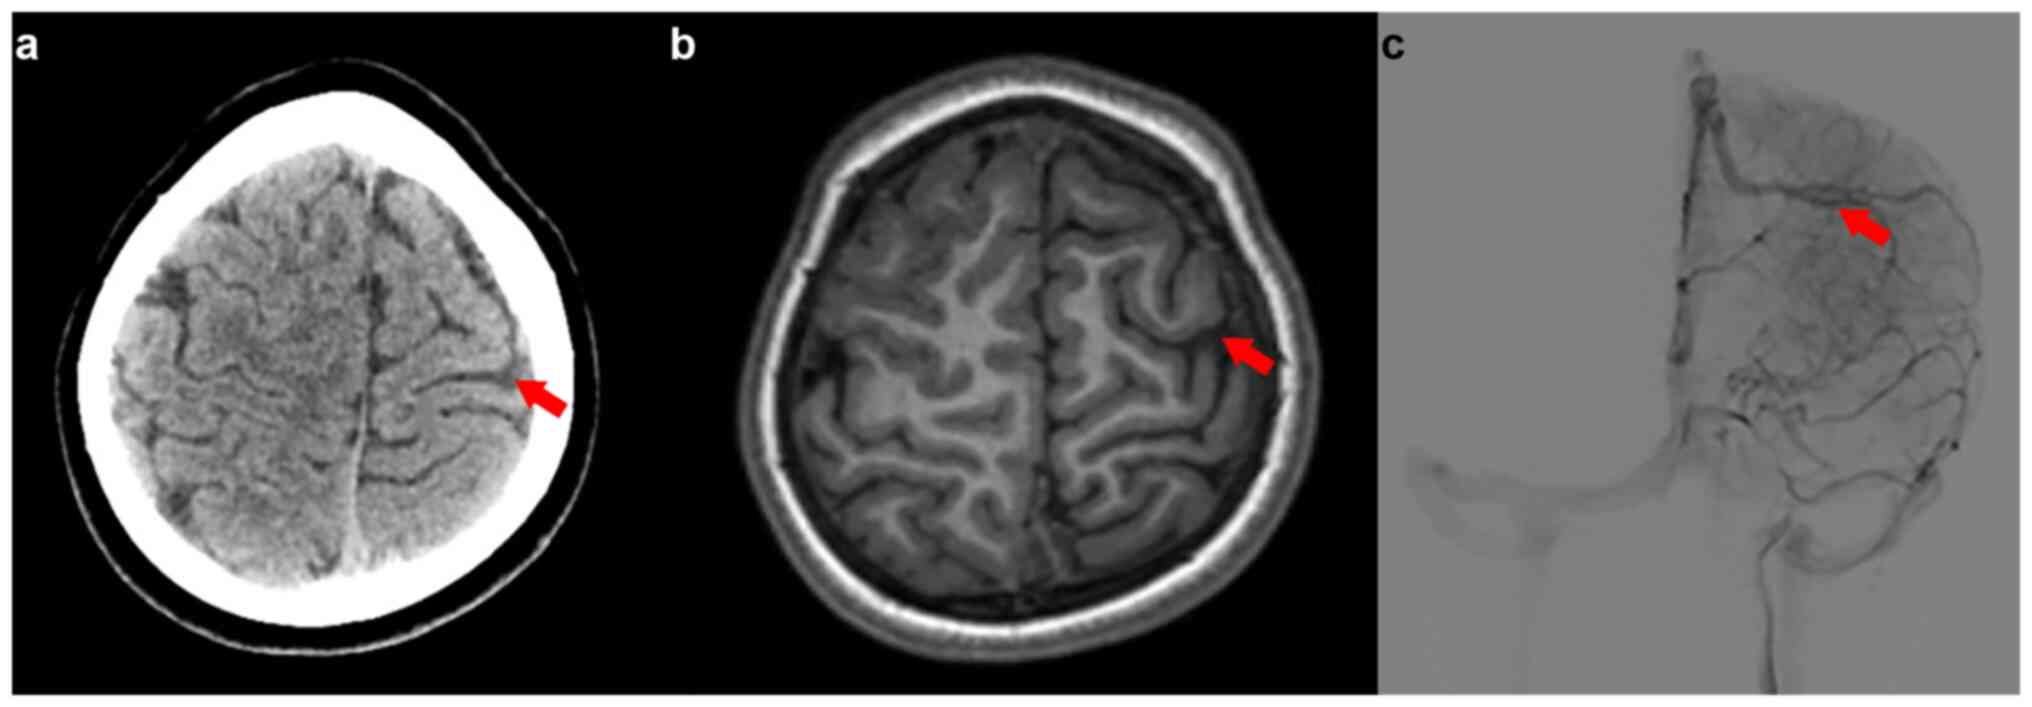

Upon presentation at the hospital, the patient was preliminarily diagnosed with epilepsy. Despite oxcarbazepine (210 mg every 12 h, orally) and perampanel treatment (3 mg nightly, orally), the seizure patterns changed, involving abrupt shakes, falls and limb tremors. No significant personal, familial or prior health issues were reported. A physical assessment revealed a conscious yet minimally responsive patient with bilateral muscle strength grade V. An EEG showed generalized or right focal myoclonic-atonic seizures (Fig. 3). MRI, MR angiography and MR venography indicated a smaller right parietal gyrus portion and localized cortical dysplasia, with multiple enhanced vascular shadows in the right parietal space suggesting vascular malformation (Fig. 4). A preoperative evaluation, including positron emission tomography (PET)/CT and skull MR fusion, localized an epileptogenic focus in the right central parietal area, indicative of focal cortical dysplasia (FCD). A craniotomy performed to resect the epileptic focus revealed a vascular mass flexion in the right parietal region. The clinical and surgical findings led to a diagnosis of SWS type III (Fig. 4). Post-surgery, the patient was enrolled in a detailed follow-up program, including visits at ~1, 3, 6 and 12 months, to closely monitor recovery and seizure activity. Over the 1-year follow-up period, the patient experienced a stable recovery and remained seizure-free. This follow-up regimen facilitated the early detection and management of any potential complications, contributing to the patient's positive prognosis. The continued absence of seizures post-surgery underscores the effectiveness of the surgical treatment and supports a favorable outlook for the patient's continued neurological health.

Figure 4

Brain magnetic resonance imaging and intraoperative image detailing abnormalities in the right parietal lobe. (a) Diminished size of the right parietal gyrus with evidence of local cortical dysplasia. (b) Enhanced vascular shadows suggesting multiple disorders in the right parietal space, pointing to vascular malformations. (c) Positron emission tomography-computed tomography scan revealing a low metabolic signal in the right posterior central gyrus. (d) Intraoperative visual field capturing a vascular mass in the right parietal area. (e) Vascular malformation in the right parietal region shows a complex network of enlarged and intertwined vessels that appear redder or sometimes deep blue, reflecting the oxygenation status within these abnormal vessels. The irregular shape of the vascular malformation is evident, with intricate paths through brain tissue clearly discernible. Surrounding the malformation, there may be signs of tissue atrophy or damage. The red arrow indicates the lesion.